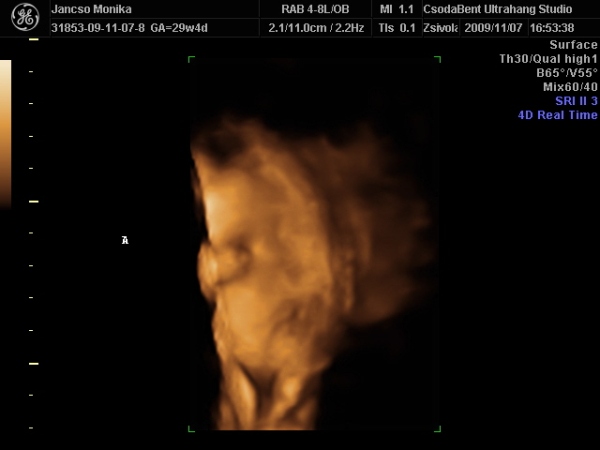

Athena, Jutka. Nilszi-nek igaza van abban, hogy sokszor nem mérnek pontosan az UH-k alkalmával. Misem bizonyítja ezt jobban , mint az én esetem. Szerdán este a rendeléses Uh-n , ahol elég lelkiismeretesen mért a szonográfusnő, ott a picur méretét: 1518g-ra becsülték ( kicsit meg is ijedtem!) A pocakja szép nagy volt AC:255mm a combcsontja, amire kétszer is rámért FL:53mm, BPD( fejátmérő):75mm HC ( fejkörfogat):266mm.

Másnap reggel mentem 4D UH-ra, ahol BPD: 72,6mm HC: 261,9mm AC: 220,2mm FL: 57,5mm becsült súly: 1108g.

Pedig ugyan arról a gyerekről van szó!!!! Nem hiszen, hogy lüktetne a pocakomban. :lol:

Hát ennyit a gépekről és a pontos méretekről!!!

Ráadásul képzeljétek hogy jártam a 4D UH-n. Zsomborka egyáltalán nem akarta megmutatni magát, nem fordult be a gerincem felé néz és annyira betakarta a karjával és a felhúzott lábacskáival magát, hogy semmit nem lehetett látni belőle. Hiába forogtam, mozgattuk a pocakom, fel sem ébredt és egyáltalán nem akart elmozdulni.

Egyetlen képet tudott csak készíteni a szonográfus, azt is csak a talpacskájáról. Nagyon csalódott voltam, mert ugye azt már tudtam, hogy egészséges nincs semmi baja, mert azt már előző nap megnézték, most csak őt szerettük volna látni. Így nagy nehezen kikönyörögtem, hogy nem jöhetnék-e vissza, hátha fordul egy kicsit. Kora délutánra kaptam még egy időpontot. Persze mondanom sem kell, hogy otthon még bukfenceztem is, hogy egy kicsit elforduljon, csokit ettem, kávét ittam ( pedig soha nem iszom )

A babóca mégsem akart elmozdulni, már majdnem azt mondta a szonográfus, hogy csinál egy képet, de hagyjuk a DVD-t mert most sem látszik semmi, mikor egyszer csak mintha halotta volna Zsimbi mégiscsak fordult egy kicsit, hogy végre szülei megcsodálhassák. Persze a kép szemcsés volt és még így is betakart a kis kezecskéje egy kicsit, de mi olyan boldogok voltunk, hogy végre látunk belőle valamit, hogy madarat lehetett volna fogatni velünk. Sőt még ásított is egyet, biztos érezte, mekkora a sikere, annak, ha kicsit produkálja magát. Így végre meg lett a várva várt DVD. Sajnos képet nem tudok róla berakni, mert a laptop-om nem szereti ezt a DVD-t és nem akarja elindítani, így csak a lejátszónkon tudom megnézni, de ott nem tudok képeket kivágni. Így csak egy képet tudok bescannel-ni, amit az Uh-osok nyomtattak ki fekete fehérben.

Kép Zsomborka 28+4

Kép Zsimbi talpacska